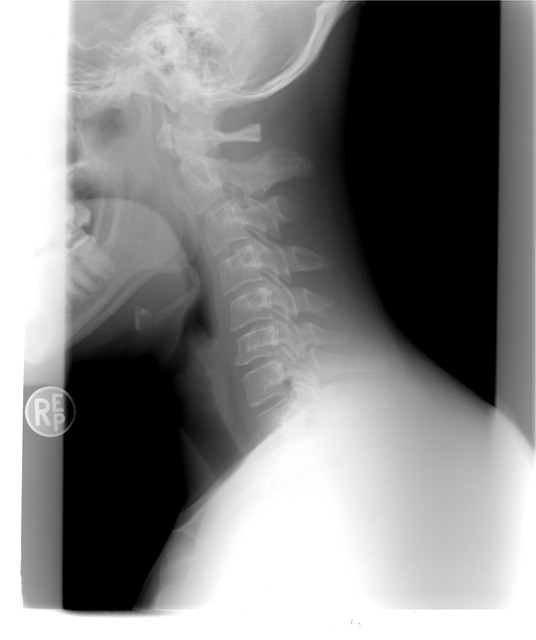

목디스크가 있는지는 진단법을 이용해서 직접 판단해볼 수 있다. 가장 먼저 디스크가 생겼을 경우 손가락이 둔감해져서 섬세함이 줄어든다. 그러므로 글씨 쓰기가 힘들거나 단추 잠그는 게 어려우면 목디스크 초기증상을 의심해야 한다. 또한 젓가락질이 힘들고 동그라미를 똑바로 그리지 못하겠다면 목디스크일 확률이 높다. 또 디스크가 생겼을 경우 목에서 팔까지 내려가는 신경을 누르면서 어깨부터 손까지 쥐가 난다. 어깨, 손에 난 쥐가 만세 자세를 하면 통증이 사라진다면 디스크 때문일 수도 있다. 실제로 목 디스크 환자가 병원 방문 시 팔을 머리위로 올린 채 진료실에 오는 사례가 보인다. 또 목 디스크가 오면 힘이 약해지기 때문에 손가락의 마디 한개마다 힘이 안들어간다. 그러므로 손가락을 붙이면 20초를 못버티고 한 개씩 떨어진다. 또한 하체의 기능이 떨어지면서 휘청거리면서 걷게된다. 더 자세히 판단하고 싶으면 바닥에 일자를 그려놓은 다음 그 위를 걸어보자. 똑바르게 걷지 못하면 목디스크를 의심해야 한다.